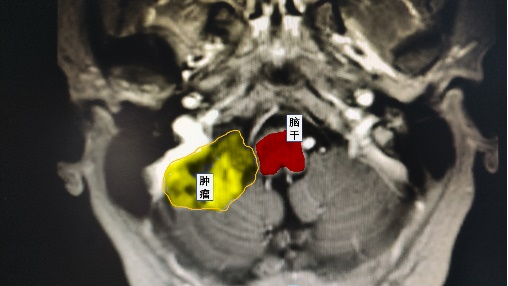

近日,鄰玉鎮(zhèn)楊女士在做體檢時(shí)意外發(fā)現(xiàn)“小腦占位”,緊貼腦干的兇險(xiǎn)位置,讓她感到驚恐和困惑。幸運(yùn)的是,她了解到瀘州市中醫(yī)醫(yī)院神經(jīng)外科與華西醫(yī)院合作,具有一流的醫(yī)療水平,便前往尋求專業(yè)的診治。

根據(jù)術(shù)前的規(guī)劃,謝勇主任通過(guò)使用神經(jīng)外科顯微鏡成功暴露出了小腦腫瘤組織,并與華西教授共同切除了緊貼著腦干和包繞顱底顱神經(jīng)的腫瘤組織。術(shù)后患者無(wú)神經(jīng)功能障礙,順利出院。